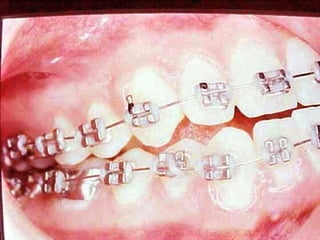

La paciente fue manejada iatrogénicamente por 5 años

Utilizando diferentes implementos ortodóncicos

La regla es clara: Laterognatias de más de 2º son quirúrgicas

La paciente fuemanejada iatrogénicamente por 5 años Utilizando diferentes implementos ortodóncicos La regla es clara: Laterognatias de más de 2º son quirúrgicas